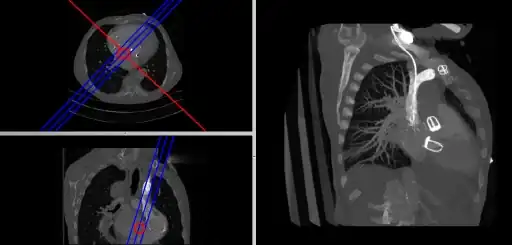

- Curved MPRs can be used for the reconstruction of more complex perspectives, as illustrated in the next figure:

- Here a curve (highlighted in green) can been positioned in the axial images (left panel) to define a curved surface which extends through the voxel data in the z-direction, and voxels from this data can be reconstructed into a two-dimensional image (right panel). Note that more complex curves than the one illustrated can be generated so that, for instance, the three-dimensional course of a major blood vessel can be isolated, or CT head scans can be planarized for orthodontic applications.